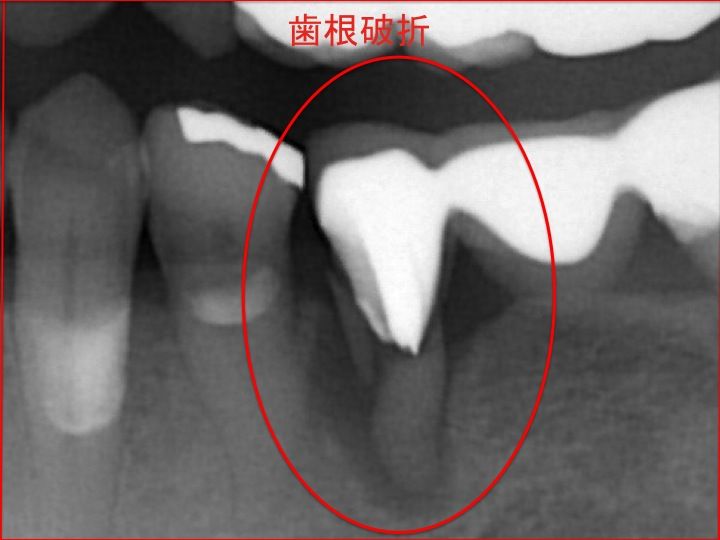

下顎左側の歯根破折 部位を拡大して見てみましょう!

拡大すると 根が折れているのが分かるかと思います。

先にも解説しましたように 神経のない歯は、非常に脆いので

このようなことが起こる確立が高くなります。